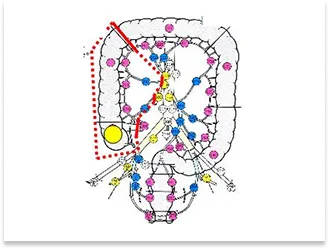

直腸S状結腸移行部の進行癌症例

手術部位

術前内視鏡写真